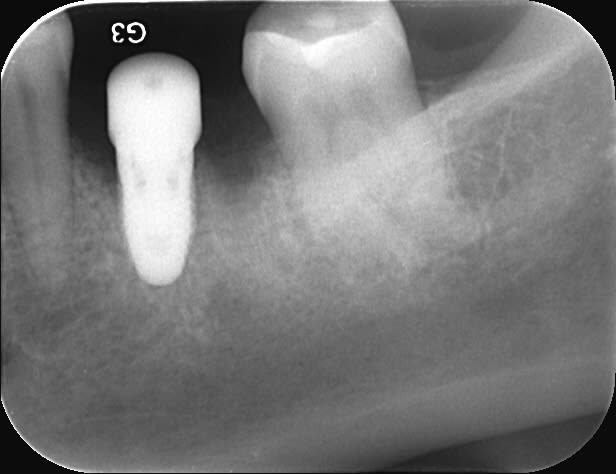

Voici 3 Rx d'un petit cas tout simple : implant Replace Nobel avec pilier titane ID.

Bite-wing fait au contrôle à 1 an. Pour ceux qui douteraient de la compatibilité parfaite :-)

1 wnn2v5 - Eugenol

2 f2qnbx - Eugenol

3 vr3ymg - Eugenol